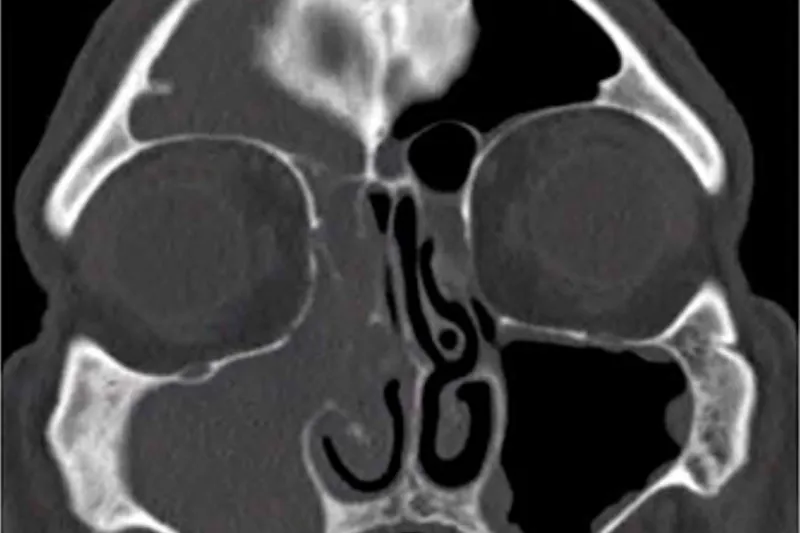

Rødderne på overkæbens præmolarer og molarer har tæt relation til bunden af sinus maxillaris, og derfor kan sygdomsprocesser eller behandlinger i disse områder føre til, at sinusbunden perforeres, så der opstår kommunikation mellem mundhulen og sinus.

3. Udredning

3. Intraorale røntgenoptagelser. Periapikale optagelser af god kvalitet. Kan eventuelt i vanskelige tilfælde suppleres med panoramaoptagelse eller CBCT.